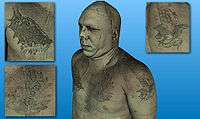

The full color visible human male dataset rendered with ImageVis3D. |